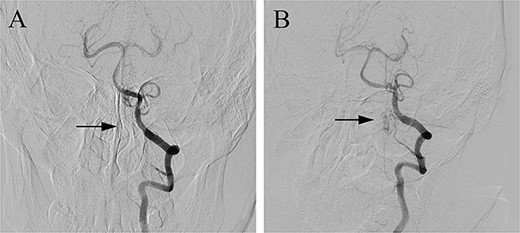

The patient underwent microsurgical treatment of the sDAVF. A minimal midline incision was made between the foramen magnum and C2. Following dissection of the arachnoid membrane, the abnormal dilated venous structure was revealed. Intraoperative indocyanine green (ICG) videoangiography was performed to identify the proximal draining vein, which was filled early with the ICG (Fig. 2A). Then we coagulated the abnormal vein close to the dural (Fig. 2B). Then the arterialized veins were darked in ICG videoangiography (Fig. 2C), preserving the draining veins to avoid spinal cord ischemia. Postoperative DSA confirmed complete obliteration of the fistula, and the patient had an uneventful recovery (Fig. 3).

Postoperative DSA (A) confirmed the complete occlusion of the fistula (arrow) when compared with the preoperative DSA (B).